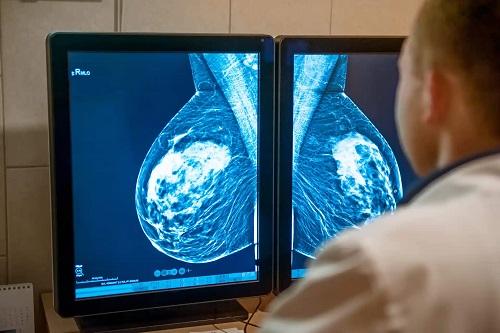

Doctorul mi-a explicat că am cancer de sân în stadiul IIB. Acesta a descoperit două tumori la sânul drept și trei tumori care au compromis ganglionii limfatici axilari din aceeași zonă. Este greu să descriu tot ce am simțit în acel moment; lumea mea s-a prăbușit.